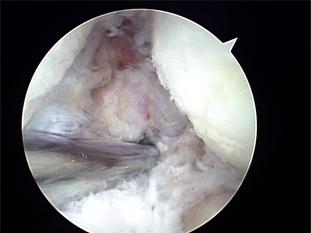

4. 수술적 치료 : 관절경으로 수술함.

외측 상과염 수술 전